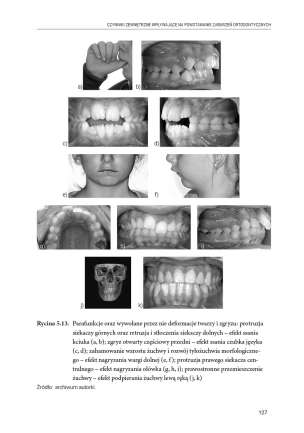

Nienormatywna wymowa, podobnie jak dysfunkcje oddychania czy połykania, często wiąże się z nieprawidłową budową narządów mowy. To dlatego, że z jednej strony struktura warunkuje funkcję, a z drugiej – nieprawidłowo przebiegająca funkcja może modyfikować rozwój anatomiczny narządu żucia, także artykulacji. Terminu „czynności prymarne” używa się w logopedii po to, by opisać właśnie takie zależności. Stoi za nim koncepcja zakładająca związki pomiędzy niewerbalnymi aktywnościami przestrzeni orofacjalnej a mową. Wykazanie tych zależności to wynik połączenia wiedzy z zakresu ortodoncji, neurologii, pediatrii, laryngologii i logopedii oraz przeprowadzonych badań, również logopedycznych.

Czynności prymarne to system powiązanych niewerbalnych aktywności odbywających się w zespole ustno-twarzowo-gardłowym, które wpływają na rozwój sprawności artykulacyjnej na każdym etapie rozwoju człowieka.

W kolejnych rozdziałach monografii są prezentowane obszary interdyscyplinarnej wiedzy – od charakterystyki anatomii i fizjologii aparatu mowy po wskazanie związków między rozwojem artykulacji (lub jej zaburzeniami) a kształtowaniem odruchów w najwcześniejszym okresie życia, właściwą postawą, a także prawidłowym oddychaniem i spożywaniem pokarmów. […] Logopedzi dostają kompendium wiedzy, która pozwoli diagnozować dziecko od okresu prenatalnego po okres dorastania, szczególnie w zakresie zaburzeń rozwoju anatomii i funkcjonowania obszarów ze sfery orofacjalnej, oraz ułatwi postępowanie logopedyczne w ich normowaniu.